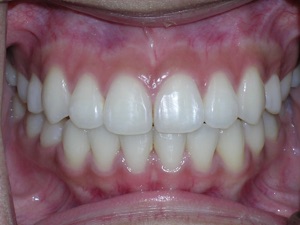

So here’s a case of an open bite, with a protrusion. There was a fair degree of crowding as well.

We decided to do porcelain brackets and have select teeth removed. Take a look.

Here are the results.